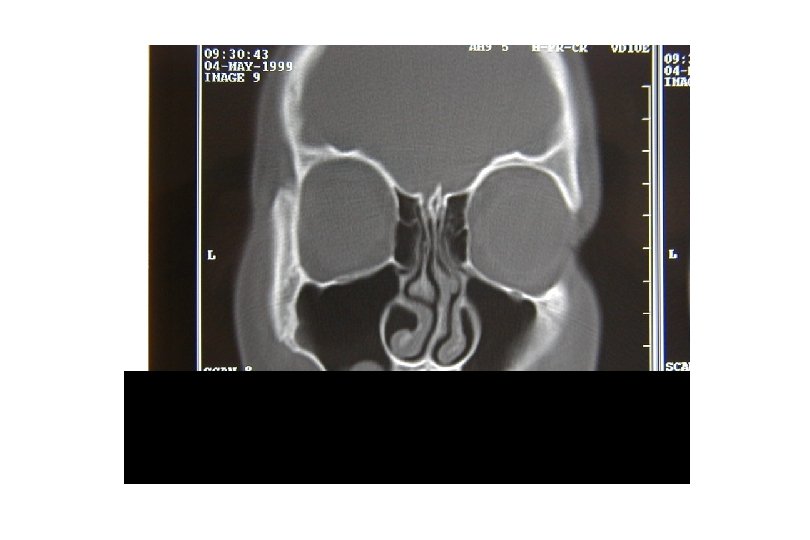

Sinusitis: Clínica * Rinorrea mucopurulenta persistete * Tos (nocturna) * Congestión nasal * Voz nasal * Dolores faciales * Cefaleas * Estrías sanguinolentas con el moco * Espasticidad bronquial repetida * RX y TC: -Engrosamiento y opacificación de las mucosas. -Niveles hidroaéreos

Sinusitis: Complicaciones * Celulitis orbitaria * Empiema epidural o subdural * Absceso cerebral * Trombosis de senos de duramadre * Osteomielitis de senos * Meningitis * Empeora asma y broncoespasmo.